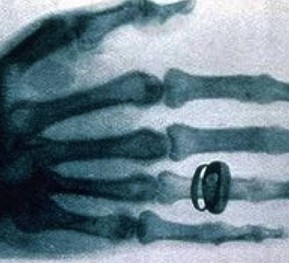

X光機主要是由X光機電源,X光球管以及控制電路等組成,是產生X光的設備,目前已廣泛應用于醫院協助醫生診斷疾病,工業的無損探傷,科學教育,機場和火車站的安全檢查等

圖像監控法是直接從x射線透視圖像構形來判斷物品的,因此,被檢物是否可疑,取決于監視器或顯示器上的圖像。顯示器或監視器上出現的不常見物或異形物,都應視為可疑物品。那些不能準確辨認的物品也應視為可疑物品,需仔細觀察,根據需要可將圖像定位分析。